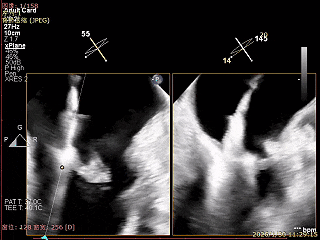

食道超声确认瓣叶夹持

经胸超声确认右冠瓣叶夹持

术前超声评估

经胸超声报告提示:患者二尖瓣2区及3区前叶关闭时脱入左房,二尖瓣重度反流(MR 4+),患者LA前后径约52mm,LVEDD约68mm,LVESD约42mm,EF值:65%,经胸超声测二尖瓣瓣口面积约6.1cm2,主动脉瓣无冠瓣脱垂并中重度反流,三尖瓣中度反流,估测中度肺动脉高压。

经食道超声精细化测量:肺静脉逆流,房间隔可穿刺高度约4.2cm,Flail宽度约21mm,Flail高度约8mm,Flail Gap约4mm, 3区AML长约23mm、PML长约12mm、2区AML约32.2mm,PML约16mm。